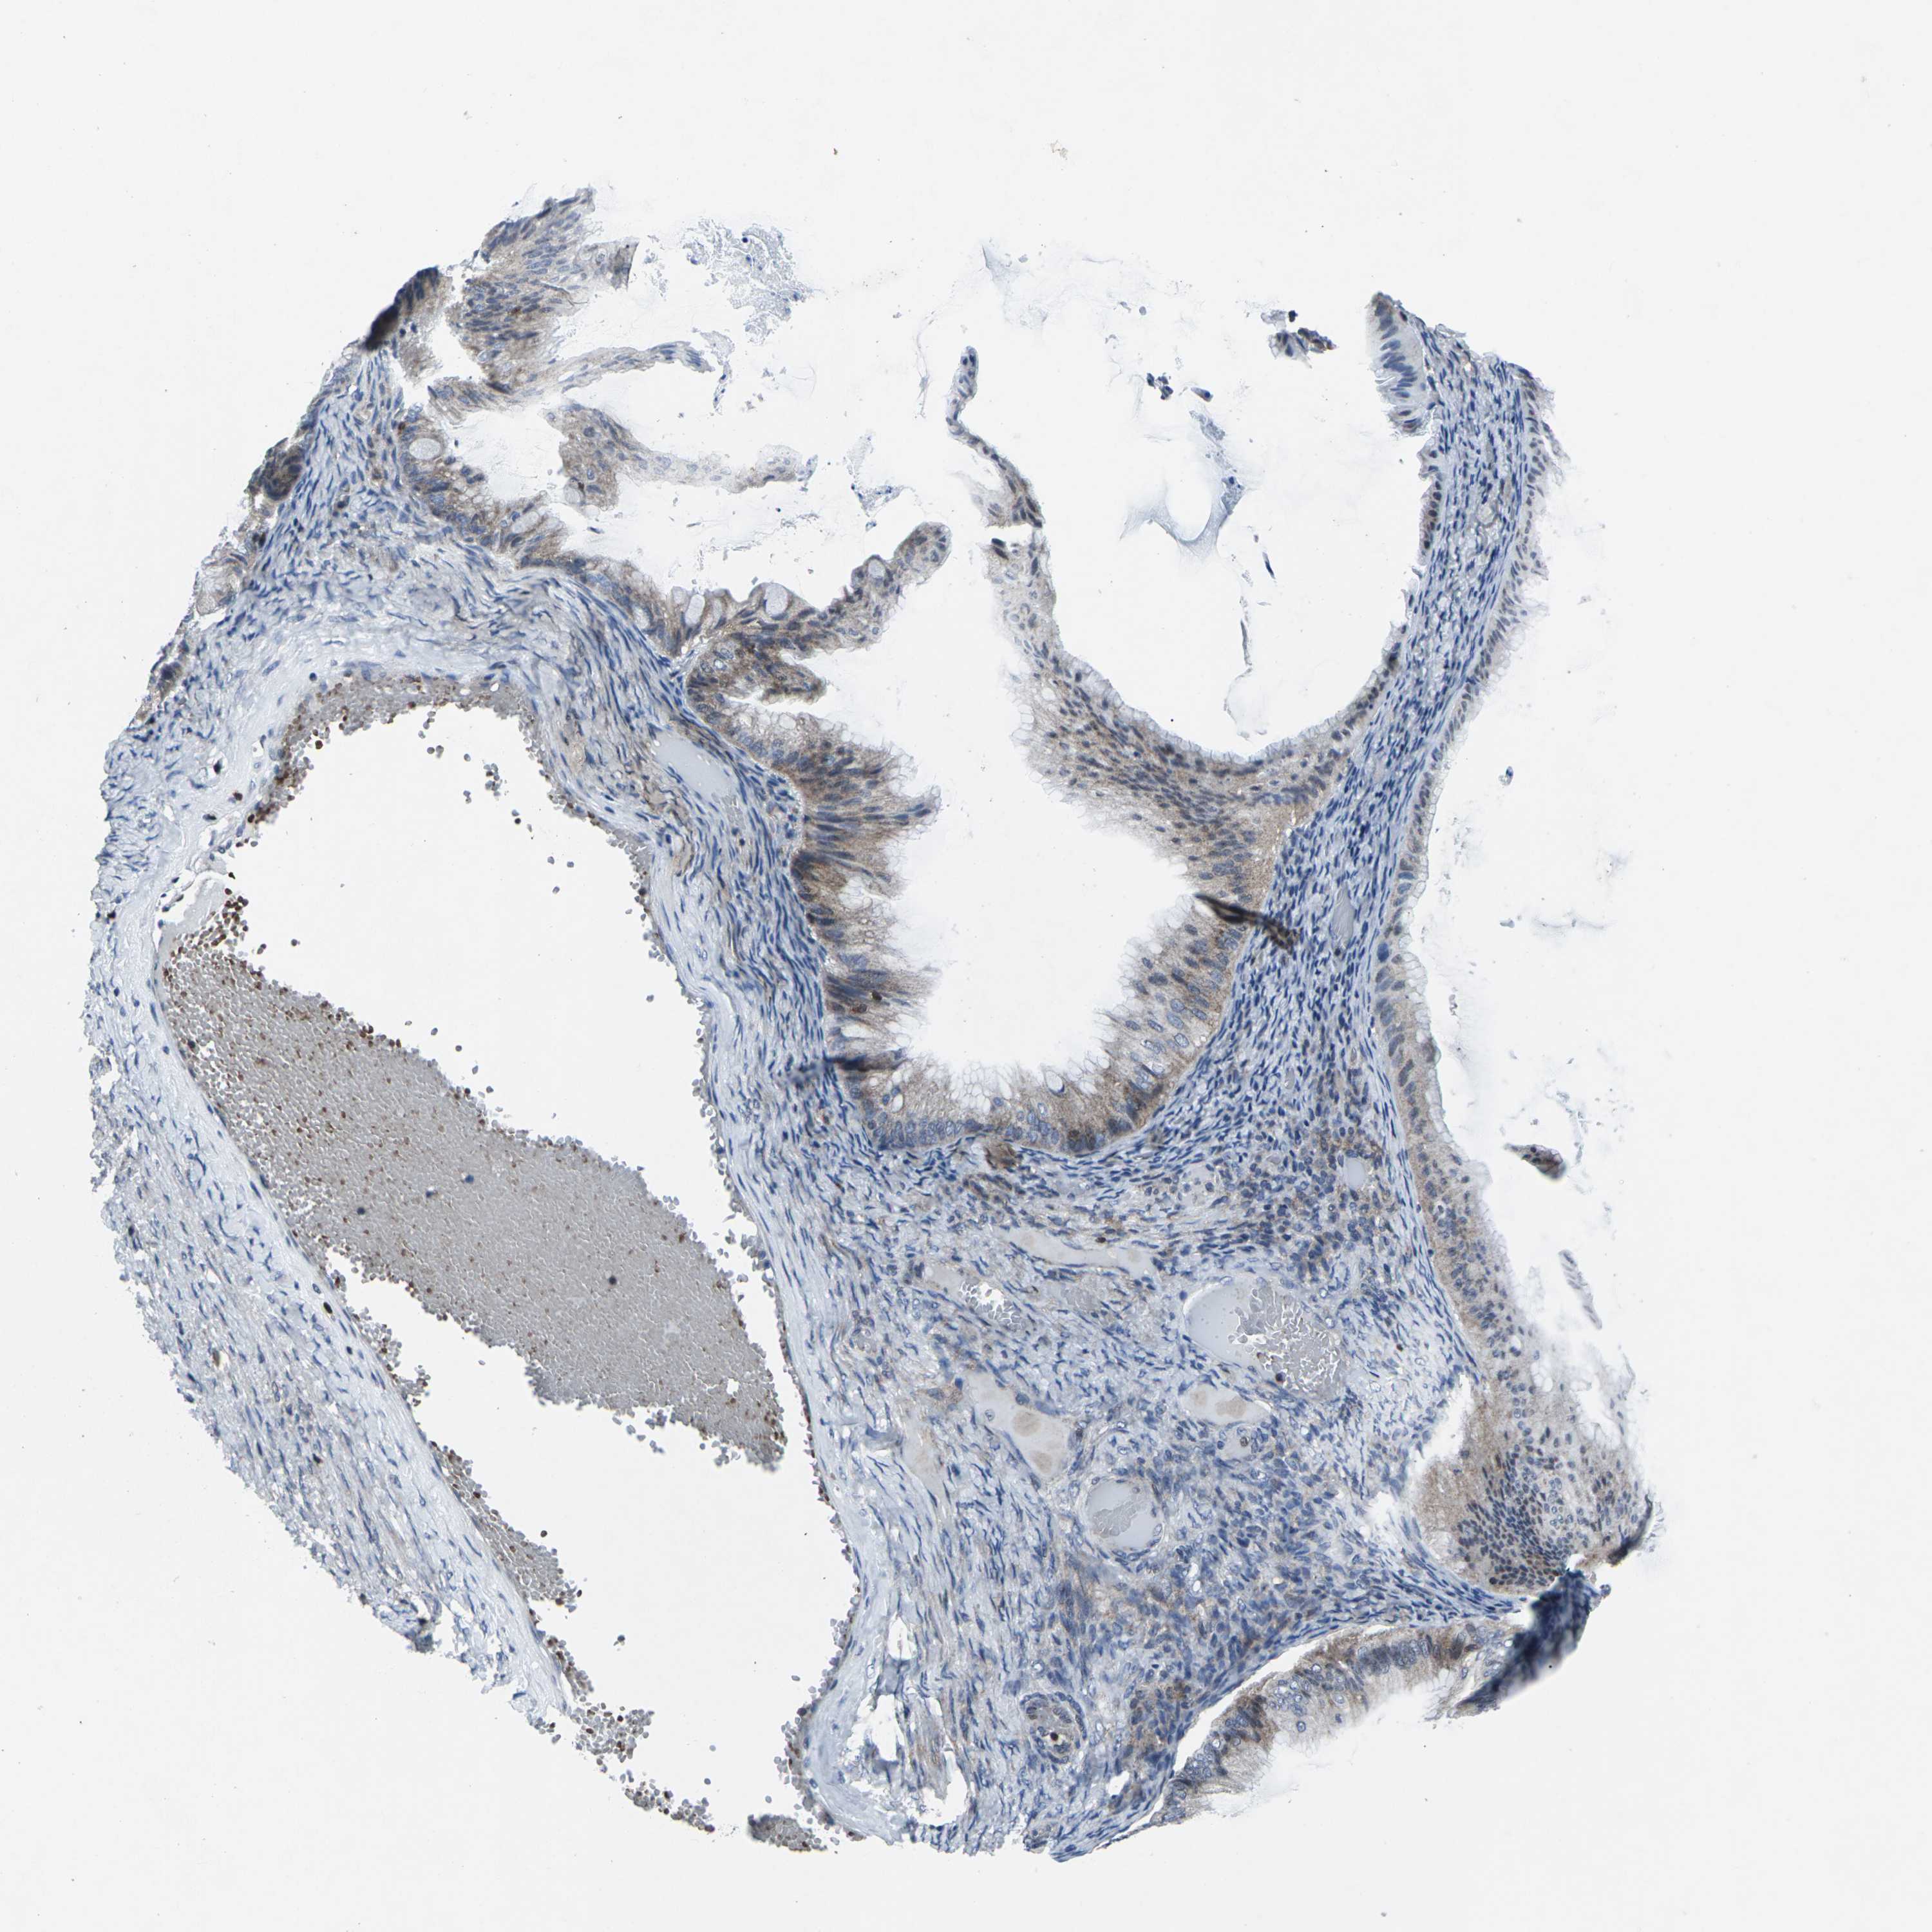

OVARIAN CANCER - Protein expressioni

A mouse-over function shows sample information and annotation data. Click on an image to view it in a full screen mode. Samples can be filtered based on level of antibody staining by selecting one or several of the following categories: high, medium, low and not detected. The assay and annotation is described here.

Note that samples used for immunohistochemistry by the Human Protein Atlas do not correspond to samples in the TCGA dataset.

Antibody stainingi

Antibody staining in the annotated cell types in the current human tissue is reported as not detected, low, medium, or high, based on conventional immunohistochemistry profiling in selected tissues. This score is based on the combination of the staining intensity and fraction of stained cells.

Each image is clickable and will lead to virtual microscopy that enables deeper exploration of all samples and also displays staining intensity scores, fraction scores and subcellular localization as well as patient and tissue information for each sample.

Antibody HPA001860

Antibody CAB013108

Cystadenocarcinoma, serous, NOS

Cystadenocarcinoma, mucinous, NOS

Carcinoma, endometroid

Carcinoma, NOS